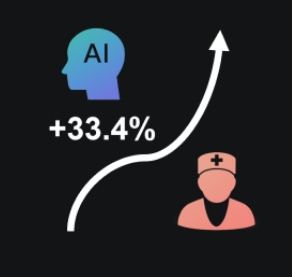

AI to Human Accuracy

Number of Breast Cancer Cases Detected

81.29

62.34

In screenings of 100,000 people, Dr. J (AI) detected approximately 30.4% more confirmed breast cancer cases than human physicians.

Blind Comparison:

AI vs. Human Doctors

In a 100% blind study, where neither AI nor human doctors knew the patients' conditions, an unbiased comparison was ensured. AI detected 33.4% more breast cancer cases in this controlled diagnostic setting.

Nurses with Dr. J (AI) vs. Ultrasound Physicians

Achieving comparable accuracy in breast cancer screening with 100% consistency in lesion Identification, addressing workforce shortages.